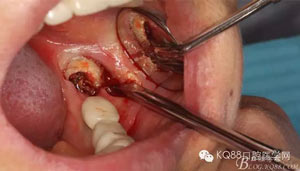

圖5.頰側做微切口、翻瓣,暴露頰側38牙體及頰側骨板。

隨著種植修復技術的普及,很多患者的口內會有種植修復體,當相鄰的種植修復體旁邊的牙齒,各種原因無法保留的時候,需要拔除,對于我們來說又是一個新的挑戰(zhàn)。首先我們要保護種植修復體不受損壞,其次是要微創(chuàng)拔除無法保留的牙齒。這樣才能最大限度的保留種植體周圍的骨量。該患者種植術前沒有及時拔除38。導致修復兩年后38齲壞,引起臨床癥狀,幸運的是沒有種植修復37,不然,拔除難度會加大很多。

通過該病例提示我們大家,下頜第二磨牙缺失,第三磨牙阻生時,如果做種植修復,最好提前拔除阻生第三磨牙。避免以后對第二磨牙的種植體產生損害。